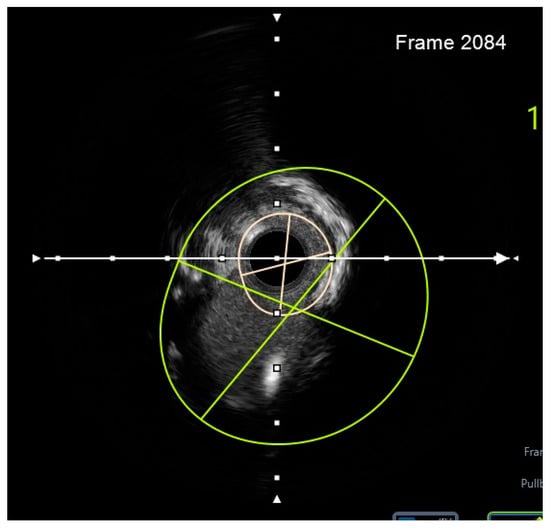

- Engage the left coronary artery with an EBU 4.0/8F guiding catheter. Wiring the three branches of the trifurcation (Floppy guide wires in LAD and RI, Hydrophilic guide wire in LCX) (Figure 14).